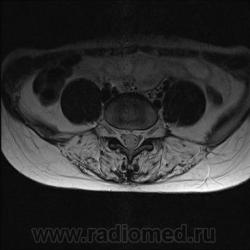

Пациентка 25 лет обратилась к неврологу с жалобами на слабость, изменение походки. Раньше не обследовалась.

каким уровням соответствуют аксиальные срезы?

obada, так точно! Срезы в данном случае значения не имеют, т.к. патологии межпозвонковых дисков нет, а мышцы одинаково выглядят на всем протяжении.

Я специально сделал изображения потемнее, чтобы выделить патологию (жировую дегенерацию) именно мышечной ткани.

В заключении я предположил болезнь Штейнерта. Хотелось бы выслушать мысли коллег.

Гм, как это я пропустил эту публикацию. Поясничные мышцы замещены жировой тканью; т.е. Они выглядят "белыми" на Т1 и Т2, в последовательности с подавлением жира, соответственно сигнал уходит; и они "тёмные". Такую картину я видел у пожилых, иногда у пациентов после операции на позвоночнике. По поводу болезни Штейнерта, должна быть клиника, изменения и гипотония/атония мышц других локализаций. На основании только МРТ ПОП не совсем убедительно. Вот небольшая ознакомительная статейка.